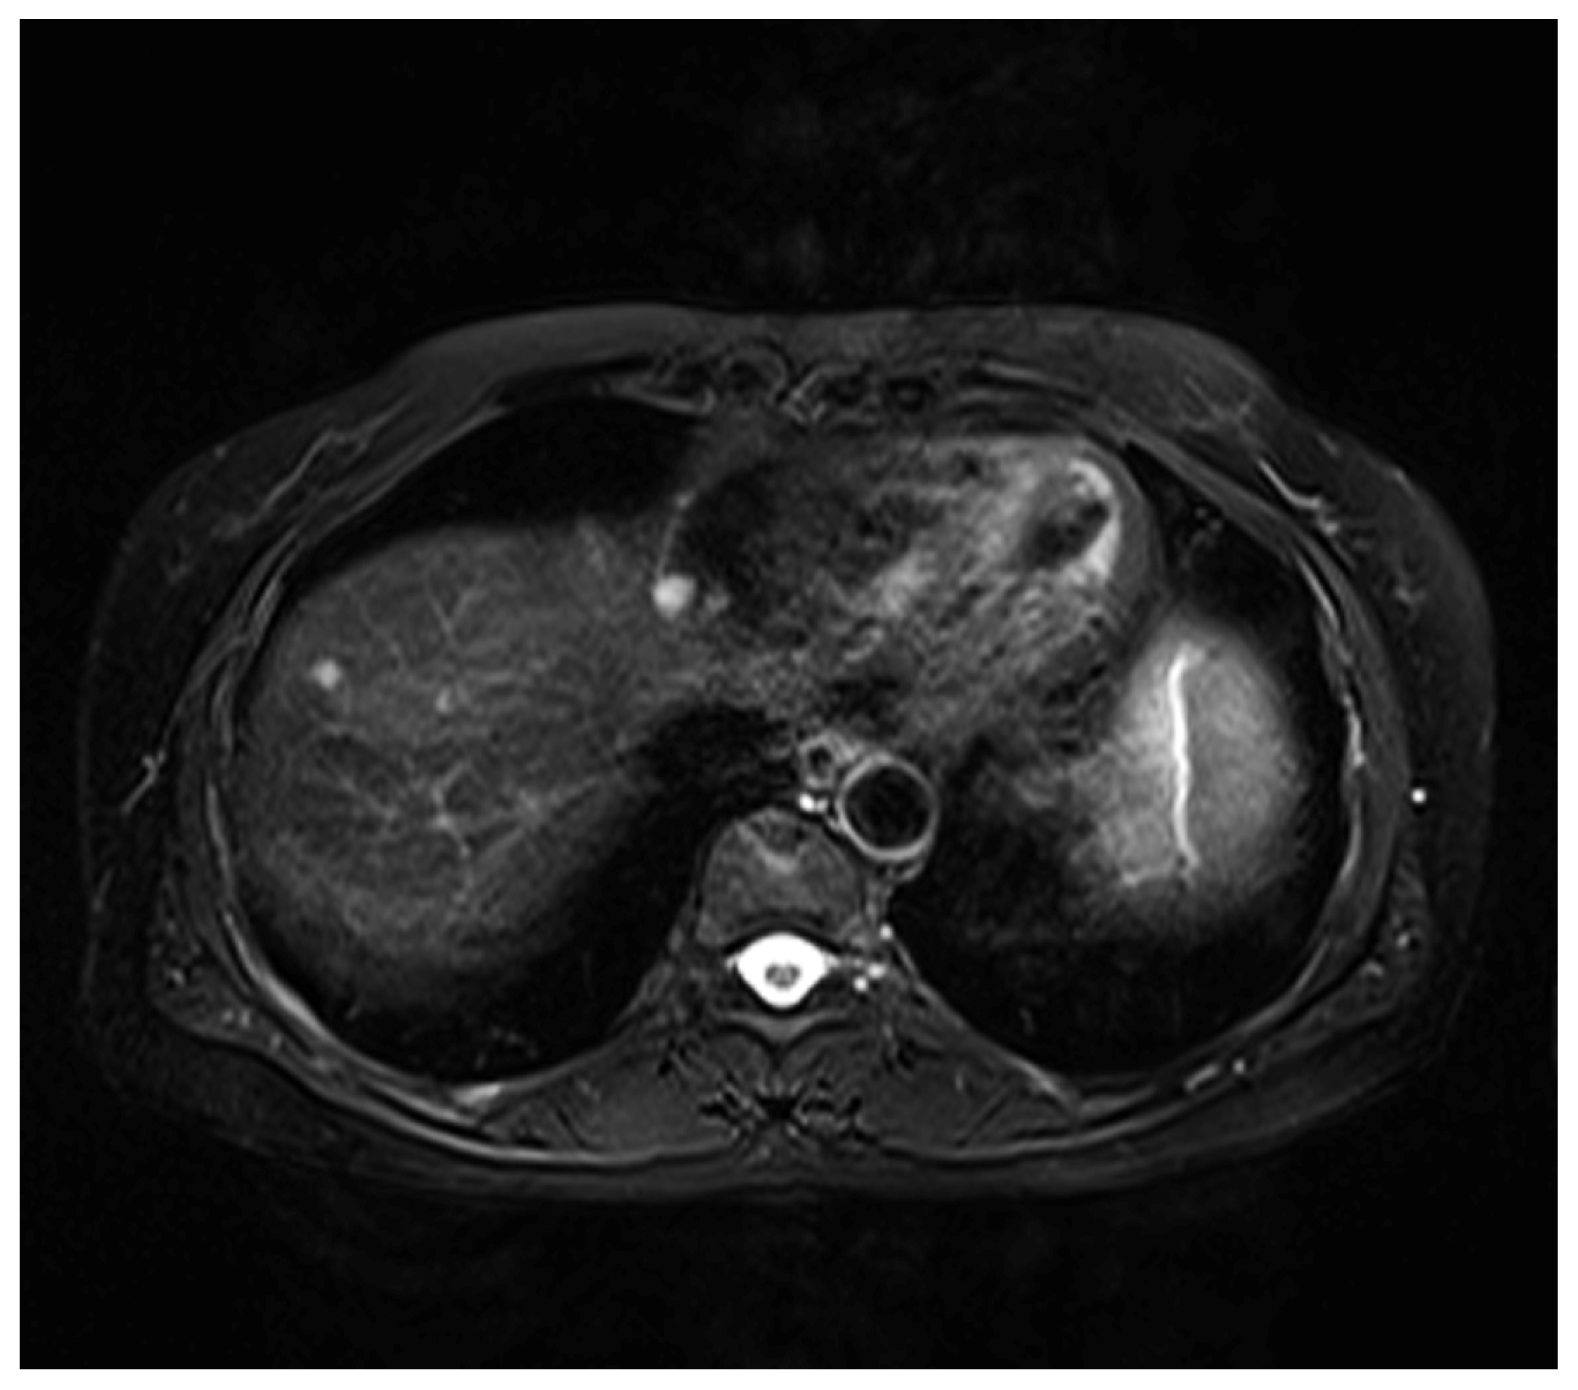

2. Case Presentation